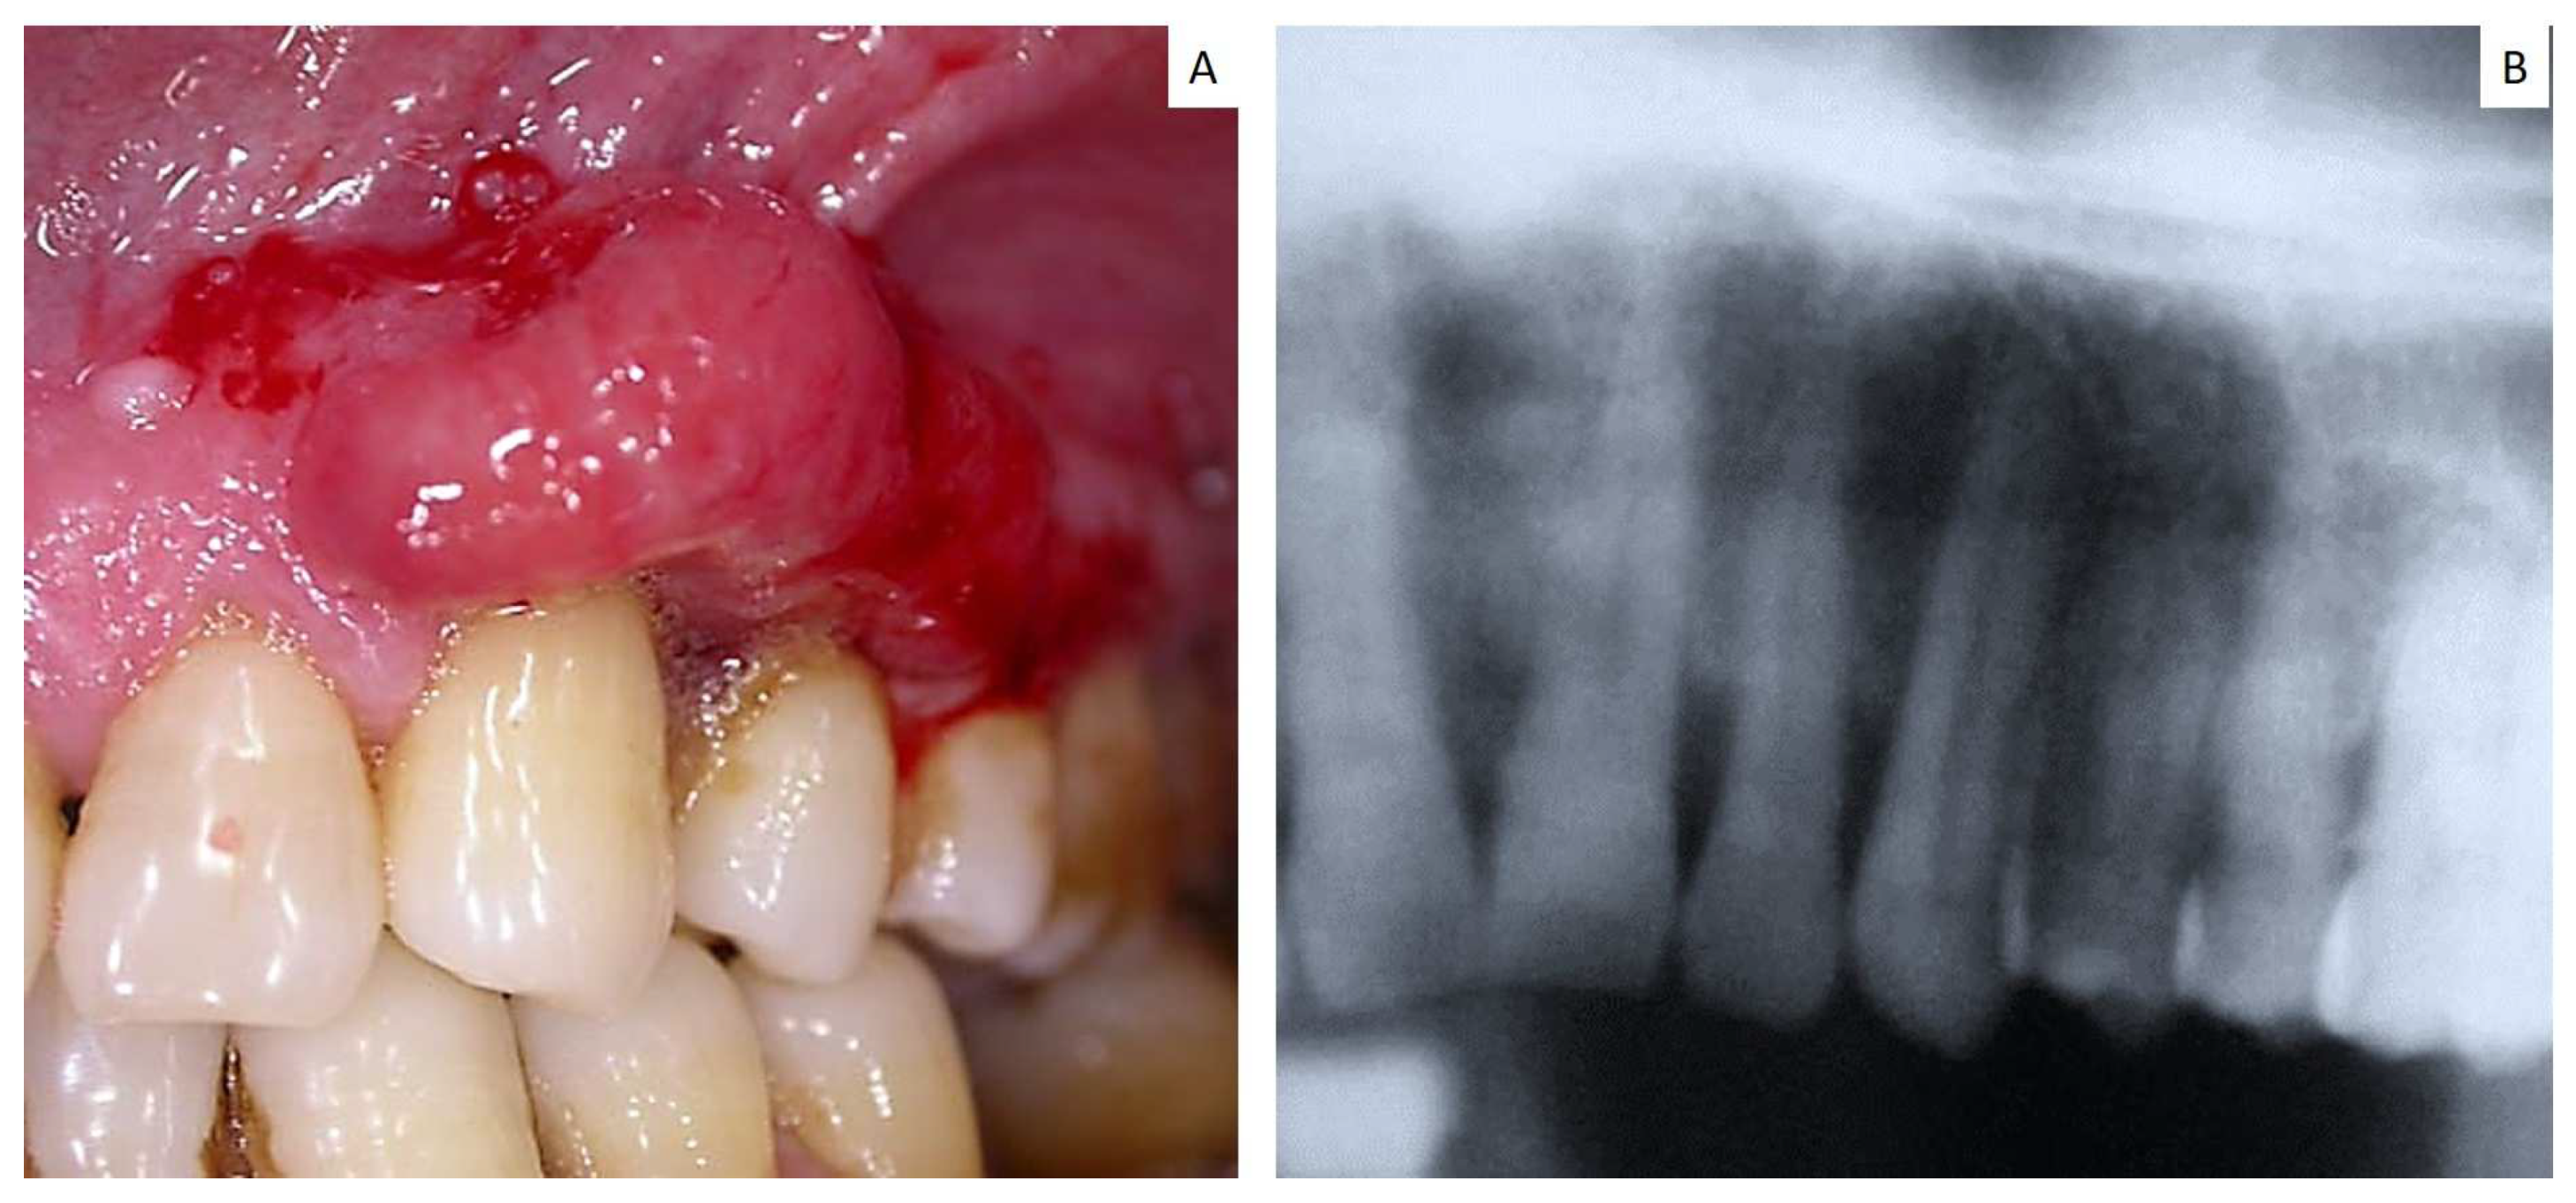

| Case | Age | Sex | Site/Sites | Primary Lung Tumor | Other Sites | First Sign of Disease |

|---|---|---|---|---|---|---|

| 15 | 67 | M | Maxillary gingiva | Squamous carcinoma | Vertebra | No |

| 16 | 65 | M | Parotid gland | Small cell carcinoma | n.a. | Yes |

| 17 | 70 | F | Maxillary gingiva Around dental implant | Small cell carcinoma | n.a. | Yes |

| 18 | 62 | M | Maxilla gingiva Around dental implant | Adenocarcinoma | n.a. | Yes |